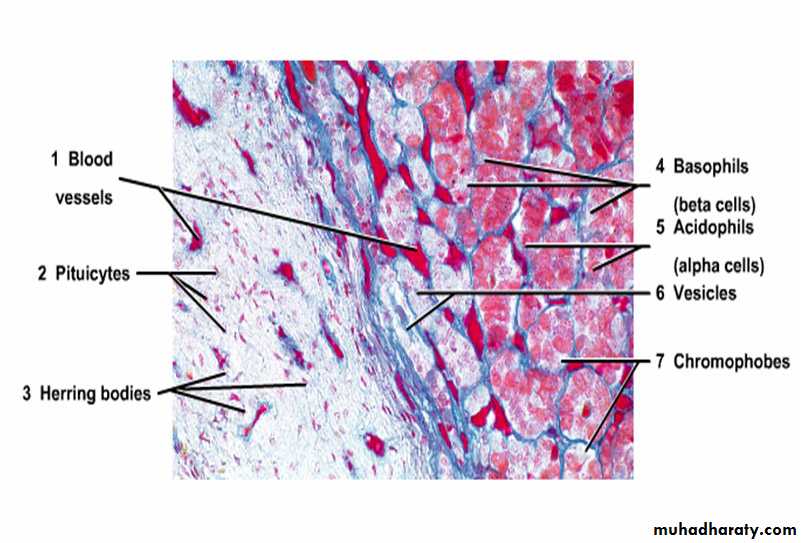

Cell types in the Hypophysis. Stain: modified azan. Oil immersion.